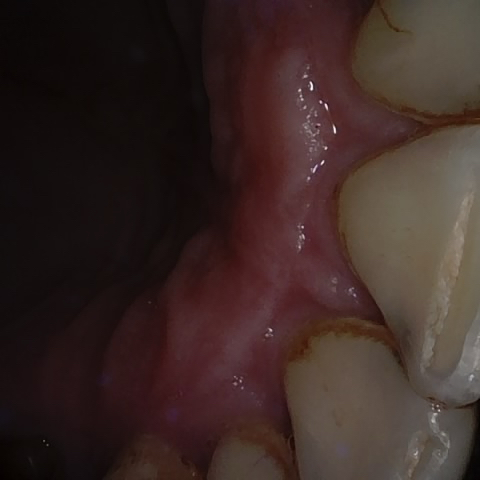

Image 361 / 1743

NHD36692

Annotated as "Good"

Original Image Rendering Image